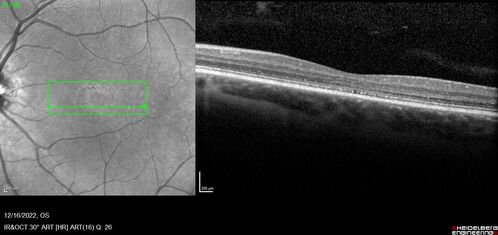

Stargardt Disease - Very Mild - 24 year old

This patient has 3 different ABCA4 mutations. His mother and sister have stargardts and his father has RP. His sisters images are also on Retinagallery.com